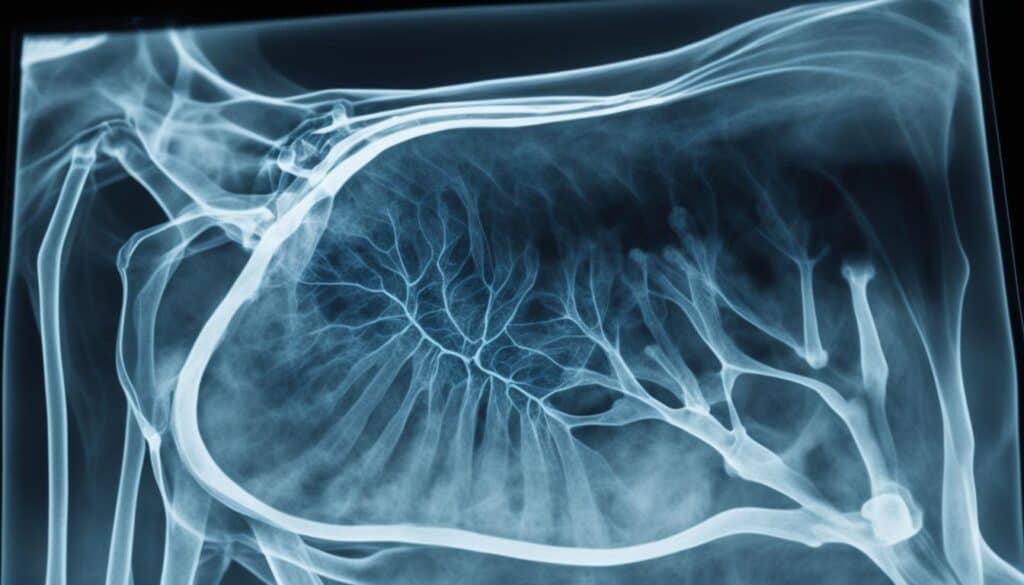

Cold Agglutinin Disease is a unique illness in dogs. It’s marked by the attack of the dog’s own red blood cells by special antibodies when it gets cold. This causes hemolytic anemia, where the red blood cells are destroyed more quickly than they can be made.

When these dogs get cold, their blood does something unusual. It starts attacking not just their red blood cells, but also those from other dogs. This problem, called agglutination, happens even at very low temperatures, with the worst at freezing point1.

Tests have shown that these dogs don’t have abnormal proteins in their blood. Yet, they release a type of antibody, known as Immunoglobulin M (IgM), from their red blood cells at warm temperatures1.

The symptoms of this disease in dogs can be seen in blood tests and physical exams. It can cause widespread blood clotting and severe tissue damage due to cold1.